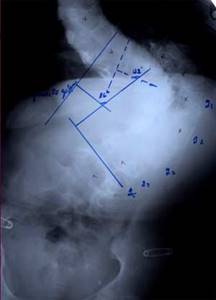

До сих пор в ортопедии принято множество методик измерения угла искривления позвоночника, и, соответственно, множество различных классификаций с разными величинами углов в градусах. Измеряется искривление так: на рентгенограмме надо провести несколько прямых линий между позвонками, а затем измерить углы между ними. В нашей стране наиболее распространена классификация, предложенная В.Д. Чаклиным. В иностранных научных источниках чаще приводится метод Дж. Кобба. Суть его заключается в следующем: на рентгеновском снимке позвоночника врач измеряет S-образное двойное искривление. В верхнем участке искривления с помощью линейки проводят две горизонтальные линии: одна над верхним позвонком, от которого идет кривизна, другая - над нижним. Если провести еще две линии, идущие перпендикулярно первым, образуется угол. Его и измеряют в градусах

Классификация выраженности сколиоза по В.Д. Чаклину (слева), по Лж. Коббу (справа) Степени тяжести сколиоза (углы искривления позвоночника, в градусах) Графический расчет на рентгенограмме: а - I степень; б - II степень; в - III степень; г - IV степень.

| По В.Д. Чаклину | По Дж. Коббу |

| I степень 180 - 175 | меньше 15 |

| II степень 175-155 | 20-40 |

| III степень 155-100 | 40-60 |

| IV степень меньше 100 | больше 60 |